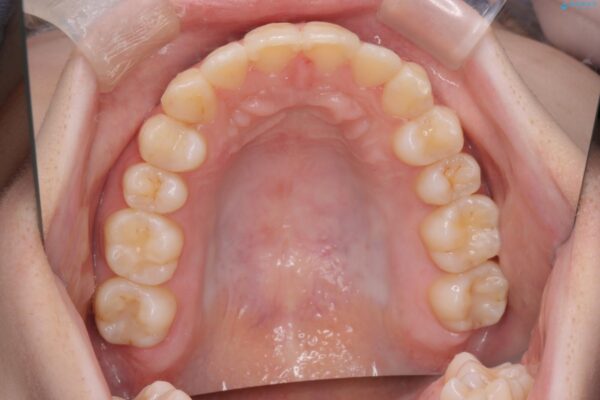

治療後

奥歯のガタつきをマウスピース矯正で改善 治療後画像 奥歯のガタつきをマウスピース矯正で改善 治療後画像 奥歯のガタつきをマウスピース矯正で改善 治療後画像